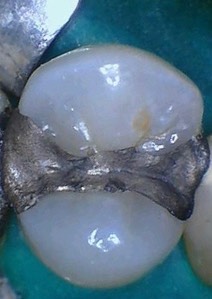

Mendel Sato #12 pre-op